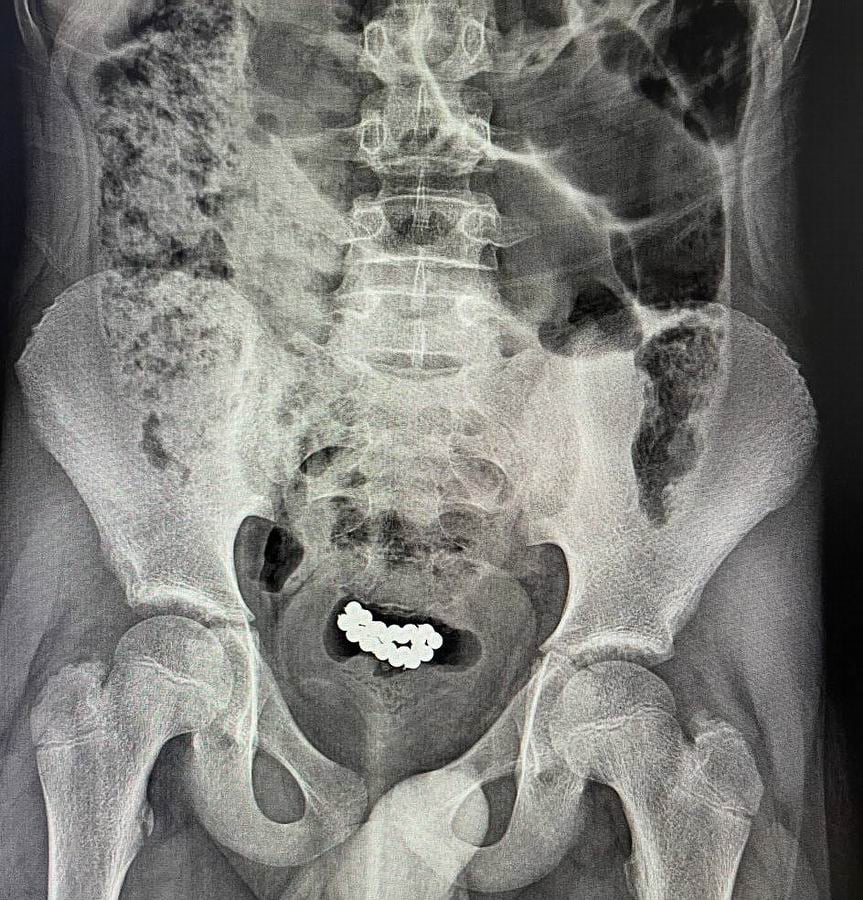

62 и 24 шарика в мочевом пузыре

"В нашем заведении успешно было прооперировано два идентичных случая эвакуации магнитных шариков из мочевого пузыря мальчиков в возрасте 10-15 лет. В обоих случаях была выполнена цистотомия мини-лапаротомным доступом с последующим изъятием 62 и 24 магнитных шариков", - говорится в сообщении.

На фото ниже врачебные снимки, на которых видно, чем чревато неосторожное обращение с игрушками.

Фото: Дети травмировались игрушкой "Неокуб" (Facebook/Волынского областного перинатального центра.)